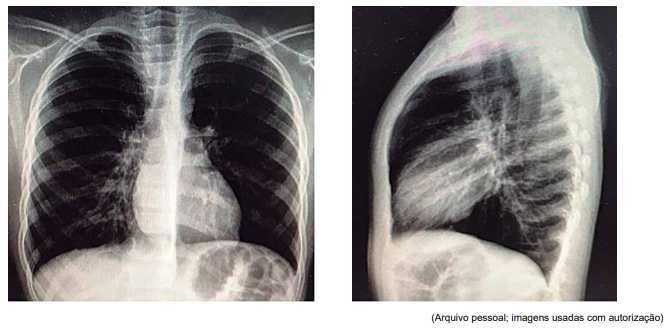

Paciente de 7 anos, com antecedente de asma de difícil controle, deu entrada no pronto-socorro com quadro de um dia de

tosse seca e taquidispneia, sem febre. À admissão, encontrava-se em mau estado geral, com FR = 66 ipm; SatO2

= 85%,

em ar ambiente, com sibilos inspiratórios e expiratórios à ausculta, com tiragens de fúrcula intercostal e subdiafragmática

graves. Foram realizadas as radiografias de tórax a seguir.

Não houve resposta com as medidas adotadas, evoluindo com tórax silente e bradipneia, sendo indicada intubação. Foi transferido, então, à UTI pediátrica com os seguintes parâmetros ventilatórios: em pressão controlada (modo assistido- -controlado), com pressão positiva expiratória final (PEEP) = 8; frequência respiratória (FR) = 28 ipm; pressão inspiratória (Pinsp) (acima do PEEP) = 13; tempo inspiratório (Tins) = 0,7 s; fração inspirada de oxigênio (FiO2 ) = 100%, com assincronia ventilatória e saturação limítrofe.